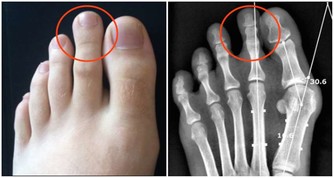

2、治療風寒骨疼、關節疼:生薑2-5克,用艾條灸之。

13、治腰肩疼痛:在熱薑水裡加少許鹽和醋,將毛巾浸濕後擰乾,敷於患處,反複數次。此法能使肌肉由緊張變鬆弛,舒筋活血,可大大緩解疼痛。